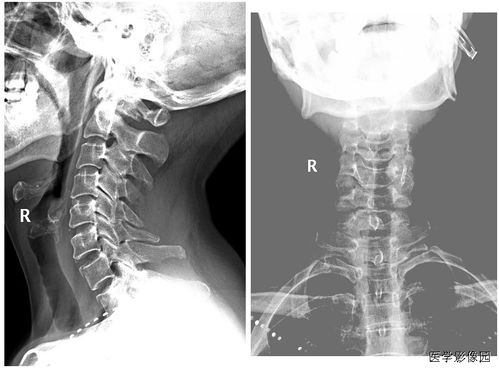

診斷手段:主要是根據(jù)臨床表現(xiàn)加上影像學檢查診斷。 (1) X線片:凡懷疑骨折者應(yīng)常規(guī)行X線檢查。

可發(fā)現(xiàn)臨床上難以發(fā)現(xiàn)的不完全骨折、深部骨折、關(guān)節(jié)內(nèi)骨折和撕脫骨折,臨床上明確骨折者也應(yīng)行X線檢查明確骨折類型及具體 情況,以指導(dǎo)治療。 (2) CT:對于骨折不明確但又不能排除者、脊柱骨折可能壓迫脊髓神經(jīng)根者及復(fù)雜骨折者 均應(yīng)行CT檢查。

三維CT重建可以更直觀便捷地進行骨折分型,對治療方案選擇幫助很大。 (3) MRI:對骨折顯示不如CT清楚,但對脊髓神經(jīng)根及軟組織、肌肉、軔帶、神經(jīng)損傷有 獨特優(yōu)點。